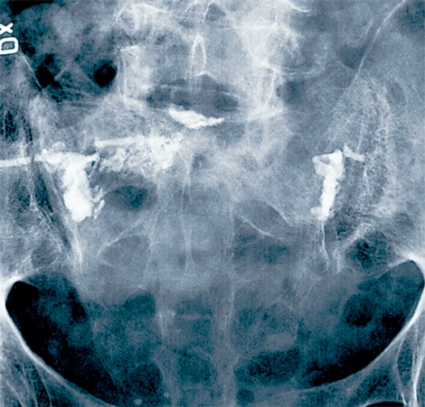

Grundprincipen bakom metoderna är att man genom en perkutant insatt kanyl fyller den frakturerade kotkroppen, eller fraktursystemet i sakrum, med bencement (polymetylmetakrylat) [7-14, 16, 17], så att fraktursystemet stabiliseras, ryggsmärtan reduceras och patientmobiliseringen underlättas. Vid vertebro- och sakroplastik cementerar man frakturerna i befintligt frakturläge (Figur 1 och 2), medan man vid kyfoplastik för in en tom ballong i kotan. Ballongen blåses sedan upp, och målet är att reducera felställningen i kotan före cementeringen (Figur 3). Denna teknik ter sig åtminstone i teorin tilltalande [14, 16]. För närmare beskrivning av metoderna hänvisas till kompletterande litteratur [6-14, 16, 17]. Såväl vertebro- som kyfoplastik kan ge upphov till en mängd komplikationer, såsom cementläckage i segmentella vener, cementläckage utanför kotan och in i spinalkanalen (med i enstaka fall parapares som följd), migration av cementkroppen efter kyfoplastik, revbensfraktur, septisk spondylit, lungödem och hjärtinfarkt. Det har hittills inte presenterats någon studie som visat att den ena metoden skulle ge färre komplikationer än den andra. Förekomsten av komplikationer måste också tas med i beaktande när man gör hälsoekonomiska utvärderingar av metoderna.

Den tredje diskuterade cementeringsmetoden är sakroplastik, som en möjlig behandling av osteoporotisk insufficiensfraktur i sakrum [15]. Dessa frakturer är ofta förbisedda, även om det rapporterats att närmare 2 procent av äldre kvinnor som lagts in på sjukhus på grund av ländryggssmärta har en sakral insufficiensfraktur [26]. Incidensen anses dessutom vara högre bland kvinnor som genomgått strålbehandling på grund av gynekologisk eller kolorektal cancer [26]. Slätröntgen missar ofta diagnosen, som vanligen ställs med skelettskintigrafi, datortomografi (DT) eller magnetkameraundersökning (MRT) [6]. Den vanligaste frakturtypen har beskrivits som en »H-fraktur«, ett benbrott med två lateralt om sakralforamina belägna vertikala frakturer som förbinds med en horisontell frakturskänkel, vanligen i S2-höjd [27]. H-fraktur ses i drygt 60 procent av fallen av insufficiensfraktur, medan unilateral vertikal fraktur återfinns i 19 procent av fallen [27].

Sedan ett decennium har behandlingsförsök gjorts med cementering även av denna frakturtyp under ledning av genomlysningsröntgen eller DT [6]. I dag finns emellertid en begränsad evidens för behandlingens effektivitet. Frey et al beskriver i en okontrollerad, prospektiv observationsstudie, inkluderande 52 konsekutiva patienter med en medelålder på 76 år, smärtreduktion i majoriteten av fallen vid sakroplastik av osteoporotiska insufficiensfrakturer [17]. Vid närmare genomgång visar det sig att tidpunkten för smärtreduktionen är oklar. Då detta är en okontrollerad studie kan man ställa sig frågan om förbättringen snarast motsvarar naturalförloppet efter en sakrumfraktur. I dag finns oss veterligen inga hälsoekonomiska beräkningar som värderar metoden.